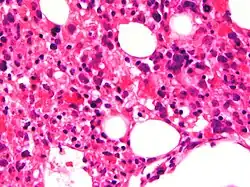

| Micrograph showing red blood cells within macrophages. H&E stain. | |

The blood count typically shows decreased numbers of blood cells—including a decreased number of circulating red blood cells, white blood cells, and platelets. The bone marrow may show hemophagocytosis. The liver function tests are usually elevated. A low level of the protein albumin in the blood is common.

Bone marrow biopsy shows histiocytosis.[20]

- Haemophagocytosis in the bone marrow, spleen or lymph nodes